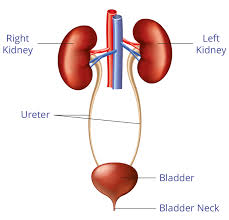

هر انسان دارای دو کلیه است که بزرگی هر یک به اندازه یک مشت است و هر کدام در یک طرف ستون فقرات در پایینترین سطح قفسه سینه قرار دارد. هر کلیه حدود یک میلیون واحد عملکردی به نام نفرون دارد. نفرون از واحد تصفیه کنندهی مویرگی به نام گلومرول تشکیل میشود که به توبول (لوله) متصل میشود. خون پس از ورود به گلومرول تصفیه میشود و مایع باقیمانده از توبول عبور میکند. در توبول آب و مواد شیمیایی بر حسب نیاز بدن به این مایع تصفیه شده اضافه یا از آن گرفته میشود و در نهایت فراوردهای به نام ادرار به دست میآید که باید از بدن دفع شود.

هر انسان دارای دو کلیه است که بزرگی هر یک به اندازه یک مشت است و هر کدام در یک طرف ستون فقرات در پایینترین سطح قفسه سینه قرار دارد. هر کلیه حدود یک میلیون واحد عملکردی به نام نفرون دارد. نفرون از واحد تصفیه کنندهی مویرگی به نام گلومرول تشکیل میشود که به توبول (لوله) متصل میشود. خون پس از ورود به گلومرول تصفیه میشود و مایع باقیمانده از توبول عبور میکند. در توبول آب و مواد شیمیایی بر حسب نیاز بدن به این مایع تصفیه شده اضافه یا از آن گرفته میشود و در نهایت فراوردهای به نام ادرار به دست میآید که باید از بدن دفع شود.